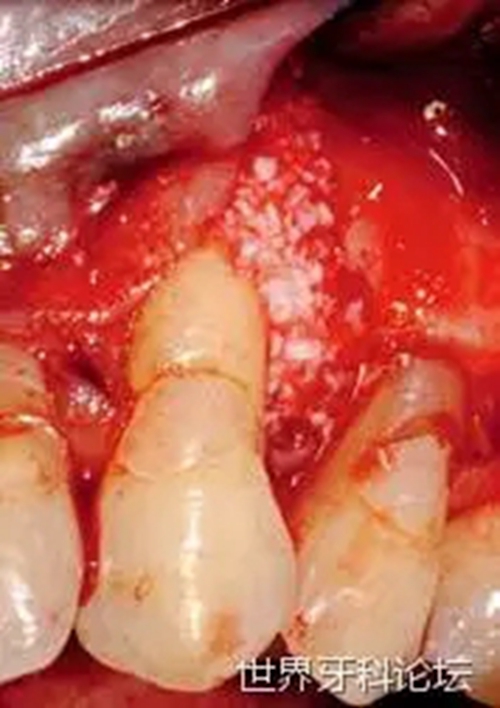

一位52歲女性患者,患局限型重度牙周炎。急性炎癥穩(wěn)定后,對(duì)患者進(jìn)行檢查,#23遠(yuǎn)中發(fā)現(xiàn)明顯的深骨內(nèi)袋(圖1)。瓣的設(shè)計(jì)同時(shí)考慮到解決目前的牙齦退縮(圖2)。仔細(xì)清創(chuàng),去除肉芽組織(圖3),之后,植入無(wú)機(jī)小牛來(lái)源羥基磷灰石(圖4)。

圖1:#23骨內(nèi)袋。

圖2:牙齦退縮。

圖3:去除肉芽組織。

圖4:植骨。

術(shù)后(圖5),術(shù)區(qū)每隔一天使用平頭Genova手機(jī)照射N(xiāo)d:YAG激光(LightWalkerATS, Fotona, Ljubljana, Slovenia),持續(xù)十天(照射5次),參數(shù)如下:0.5W,10Hz,MSP模式,每位點(diǎn)60s(圖6)。術(shù)區(qū)愈合順利,疼痛及腫脹均較輕微。6個(gè)月后復(fù)查顯示植入骨和軟組織均穩(wěn)定(圖7)。